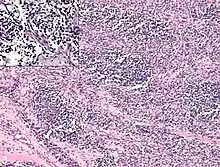

Rhabdomyosarcoma cells.

Diagnosis

Rhabdomyosarcoma is often difficult to diagnose due to its similarities to other cancers and varying levels of differentiation. It is loosely classified as one of the small-blue-round-cell tumors due to its appearance on an H&E stain. Other cancers that share this classification include neuroblastoma, Ewing sarcoma, and lymphoma, and a diagnosis of RMS requires confident elimination of these morphologically similar diseases.[15] The defining diagnostic trait for RMS is confirmation of malignant skeletal muscle differentiation with myogenesis (presenting as a plump, pink cytoplasm) under light microscopy.[5] Cross striations may or may not be present. Accurate diagnosis is usually accomplished through immunohistochemical staining for muscle-specific proteins such as myogenin, muscle-specific actin, desmin, D-myosin, and myoD1.[26][35][36] Myogenin, in particular, has been shown to be highly specific to RMS,[37] although the diagnostic significance of each protein marker may vary depending on the type and location of the malignant cells. The alveolar type of RMS tends to have stronger muscle-specific protein staining. Electron microscopy may also aid in diagnosis, with the presence of actin and myosin or Z bands pointing to a positive diagnosis of RMS.[5][35] Classification into types and subtypes is accomplished through further analysis of cellular morphology (alveolar spacings, presence of cambium layer, aneuploidy, etc.) as well as genetic sequencing of tumor cells. Some genetic markers, such as the PAX3-FKHR fusion gene expression in alveolar RMS, can aid in diagnosis. Open biopsy is usually required to obtain sufficient tissue for accurate diagnosis. All findings must be considered in context, as no one trait is a definitive indicator for RMS.